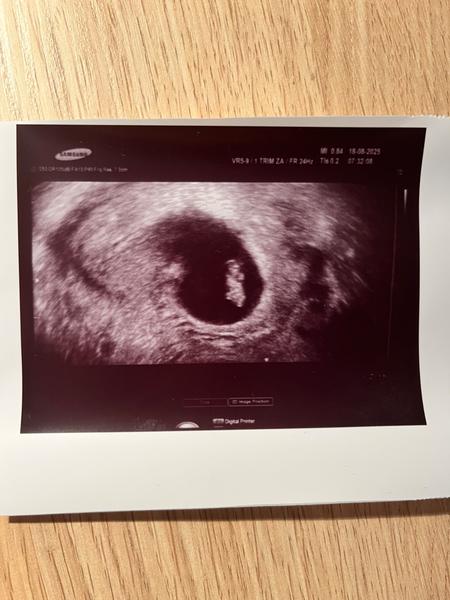

Ahojte, kto sa vyznáte, kde presne je na tejto fotke žĺtkový vak? To je ten útvar nad embryom? A embryo je ako keby hlavou otočené doľava, aj rukami a nohami? Ďakujem

@anonym_autor Ta čierna machula by mala byť gestacny vak a to biele v čiernej machuli je plod. Predpokladám, že srdiečko už bolo viditeľné tiež. Gratulujem ;)

Ešte dodám, je to 7+4 tt